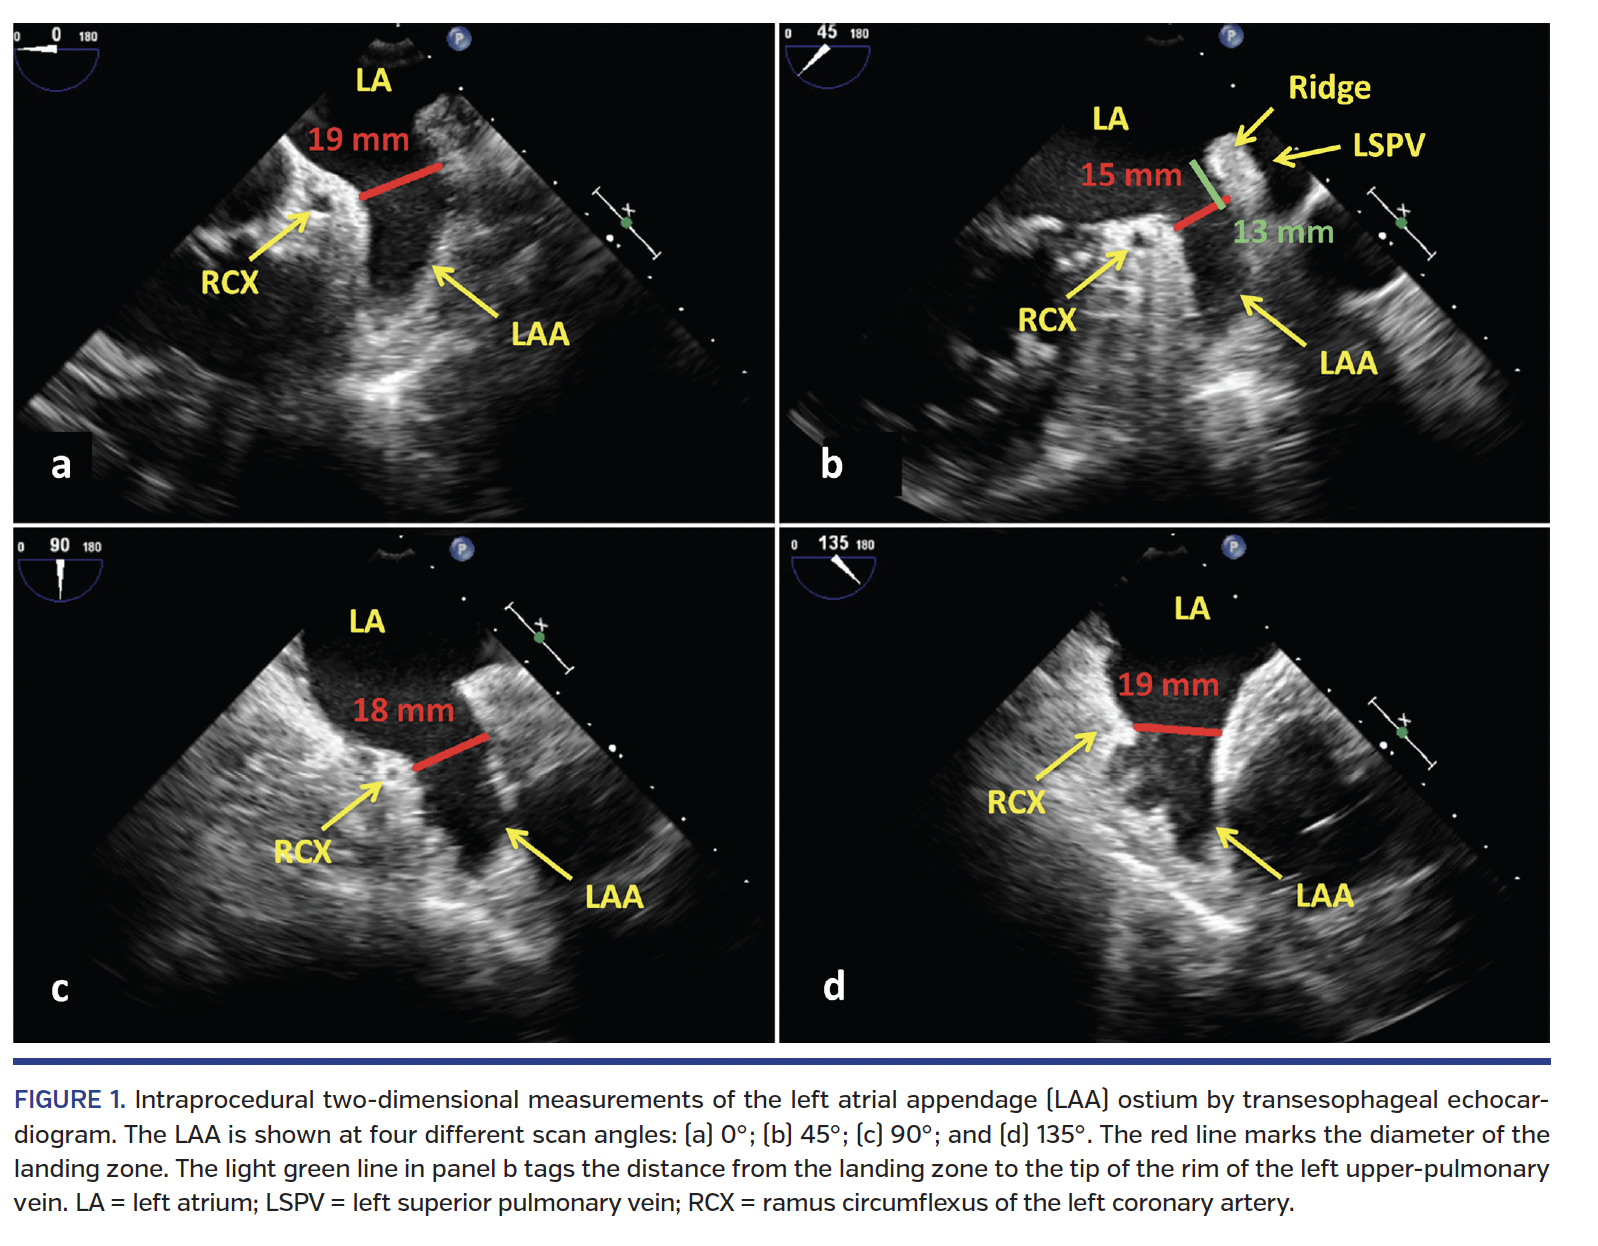

Peri-interventional echocardiography. During the LAA occlusion procedure, 2D-TEE and 3D-TEE were performed by an experienced echocardiographer with a commercially available echocardiographic system (iE33; Philips Medical Systems). In order to determine the maximal diameter of the occluder landing zone, the LAA was scanned at four different 2D views (search angles 0°, 45°, 90°, and 135°) (Figure 1). In all four views, measurements of the ostial diameter were performed from the inferior aspect of the ostium at the level of the circumflex artery to the opposing edge approximately 1-2 cm distally to the tip of the rim to the left upper-pulmonary vein (Figure 1).15 Care was taken to undergo measurements when the diameter appeared largest (ventricular systole for patients in sinus rhythm). The maximal diameter of the four measurements was used for device sizing.

Procedural details. CT imaging was not performed routinely prior to LAA occlusion. All procedures were performed under conscious sedation with simultaneous fluoroscopic and TEE guidance. Presence of thrombus within the LAA was ruled out prior to transseptal puncture in all patients; most of the patients had not undergone TEE prior to the periprocedural echo analysis in order to minimize the risk of esophageal bleeding and to avoid patient discomfort associated with repeated TEE exams. After visualizing the LAA in fluoroscopy (right anterior oblique caudal view) and TEE (0°, 45°, 90°, 135°, and 3D) (Figure 1), the device size was chosen according to our local algorithm aiming for 15%-30% compression (“2 sizes up”) (Table 1).13 After deployment, a tug-test was performed and sealing as well as compression of the device were assessed by TEE. In case these implantation criteria were not met, the device was either recaptured and repositioned, or another device size was chosen. During the procedure, unfractionated heparin was administered in order to maintain an activated clotting time >250 sec. The patients were discharged on dual-antiplatelet therapy until TEE follow-up approximately 3 months after the implantation documented permanent sealing of the LAA and no thrombus on the device. Patients were then switched to aspirin monotherapy until 1 year after the procedure.